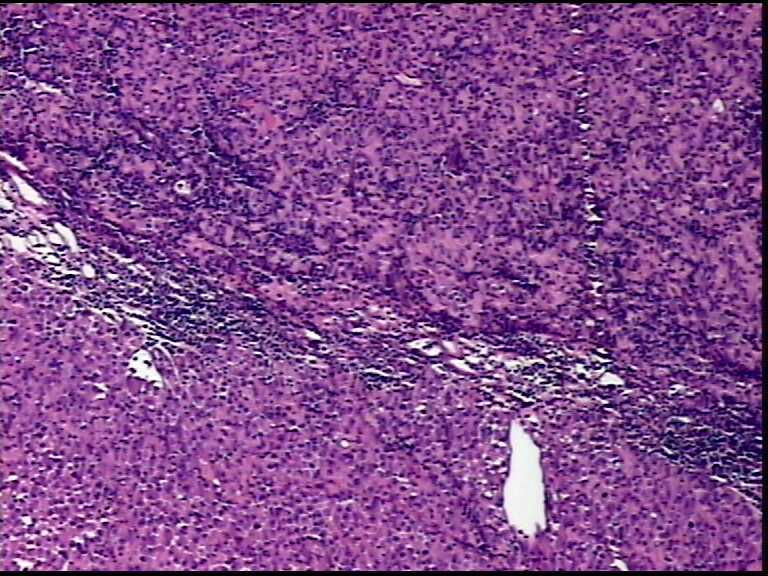

患者男性,34岁,临床没给提供,该患者梅毒阳性

• 请各位老师会诊一下 颌下淋巴结图4

图4

颌下淋巴结肿大,送检肿物直径2.5cm,切面灰粉色,质地嫩,先做了个LCA瘤细胞阴性

淋巴结内见大量宽而嗜酸性胞浆的肿瘤细胞,瘤细胞核大,偏心分布,核仁明显,成上皮样表现,部分似有腺泡样排列,符合淋巴结转移性恶性肿瘤,首先除外转移癌,恶性黑色素瘤,继而除外浆细胞瘤(岁数不太符合),横纹肌肿瘤等。

淋巴结内见大量宽而嗜酸性胞浆的肿瘤细胞,瘤细胞核大,偏心分布,核仁明显,成上皮样表现,部分似有腺泡样排列,符合淋巴结转移性恶性肿瘤,首先除外转移癌,恶性黑色素瘤,继而除外浆细胞瘤(岁数不太符合),横纹肌肿瘤等。同意楼上的观点。